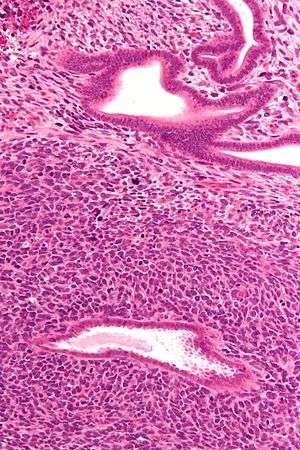

| Micrograph of a uterine adenosarcoma showing a mitotically active malignant stroma and benign glands. H&E stain. | |

Uterine adenosarcoma have, by definition, a malignant stroma and benign glandular elements. The World Health Organization (WHO) criteria have a mitotic rate cut point; however, this is often disregarded, as bland-appearing tumours with a low mitotic rate are known to metastasize occasionally.[2]